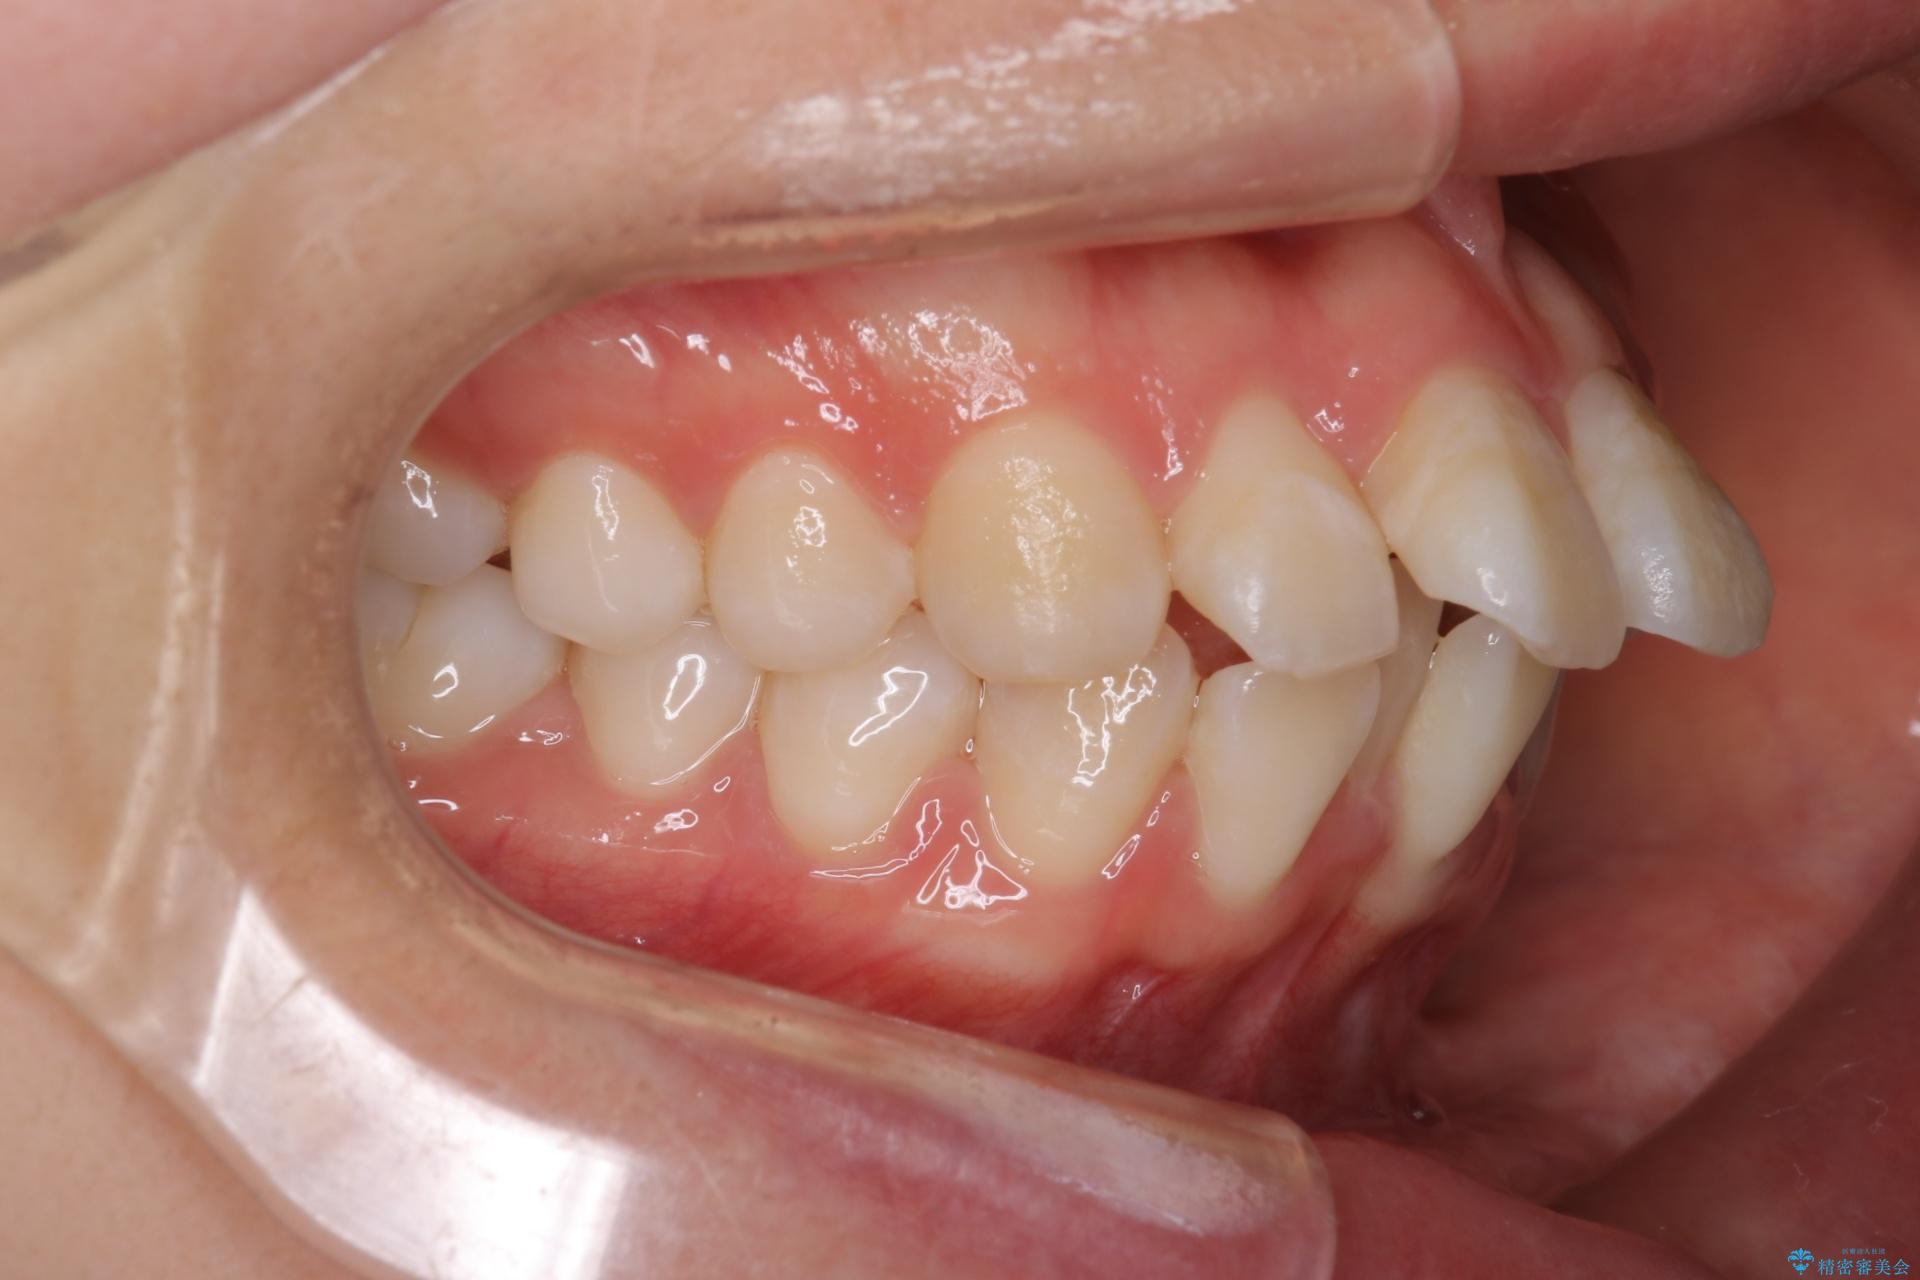

前歯のガつきと口元が出ていることを気にされご来院された患者様です。

上下4番目の歯を抜歯してガタつきを改善しながら口元を下げる治療計画を立てました。

抜歯矯正で口元を下げたことで、Eラインが大変綺麗になりました。